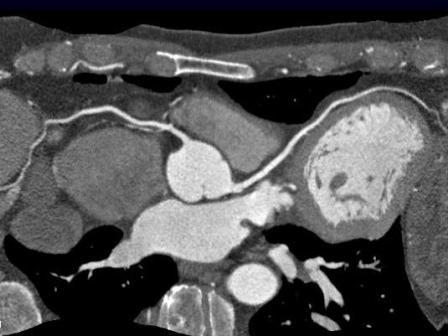

Em maio deste ano, foi publicado um artigo1 sobre troca de valva aórtica transcateter (transcatheter aortic-valve replacement – TAVR) em…